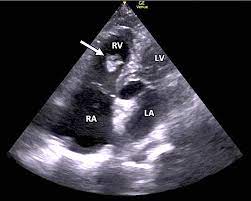

However, some researchers [15, 32] have shown that well-trained models do not perform well when the testing images come from a different statistical distribution from the training images. This domain shift problem is common in real-world medical diagnosis since medical images at various steps of the clinical procedure are often obtained with different physical properties [6]. For instance, Magnetic Resonance Imaging (MRI) and Computed Tomography (CT) play complementary roles in cardiac disease diagnosis while also exhibiting different appearances (See Fig. 1). That difference post challenges for analyzing the MRI and CT images in clinical diagnosis.

MS-CMRSeg Dataset contains 35 labeled bSSFP CMR 3D images and 45 labeled 3D LGE-MRI images, which are also not paired. Each image is cropped to a size of 192192.

Similar to [33, 34], we include the following three structures in MS-CMRSeg dataset for segmentation: the myocardial (MYO), the left ventriculus (LV), and the right ventriculus (RV). In MM-WHS Dataset, we include five structures: the myocardial (MYO), the left ventriculus (LV), the right ventriculus (RV), the left atrium blood cavity (LA), and the right atrium blood cavity (RA). For both datasets, We remove the LGE-MRI ground truth during bSSFP to LGE-MRI experiments, remove the bSSFP ground truth during LGE-MRI to bSSFP, and remove the MRI ground truth during CT to MRI experiments. The train-test split strategy is consistent with [5, 2, 33, 34]